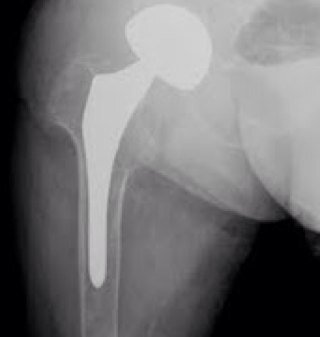

Condrosarcoma de Fémur distal, tratado Qx mediante Resección y Reconstrucción con Megaprotesis de Rodilla. En SEFEx-CR2019 tendremos una Mesa de Actualización de Cirugia Reconstructiva en Patología Tumoral dirigida por el @PabloPuertas7 y el @DrValcarcel #traumatologia @soycot